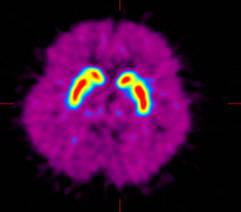

图2,早期PD患者,碳11-CFT显像,左侧壳核摄取减低